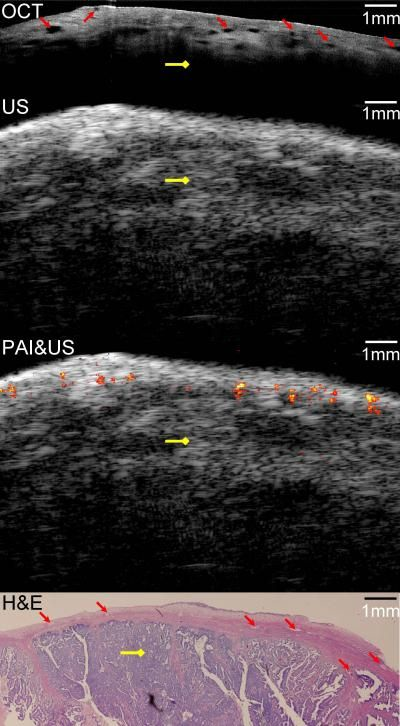

Described by the team in the September issue of Biomedical Optics Express, the diagnostic device combines the contrast provided by photoacoustic imaging, the high-resolution subsurface imaging provided by OCT, and the deeper tissue imaging provided by pulse-echo ultrasound. They tested their device by imaging both pig and human ovarian tissue, and correctly identified malignant tumors that were later confirmed by staining the tissue and examining it under a microscope. These initial tests were performed on tissue that had been surgically removed, but the device's 5 mm diameter is small enough that it could potentially be inserted through a small slit to image tissue in live patients.